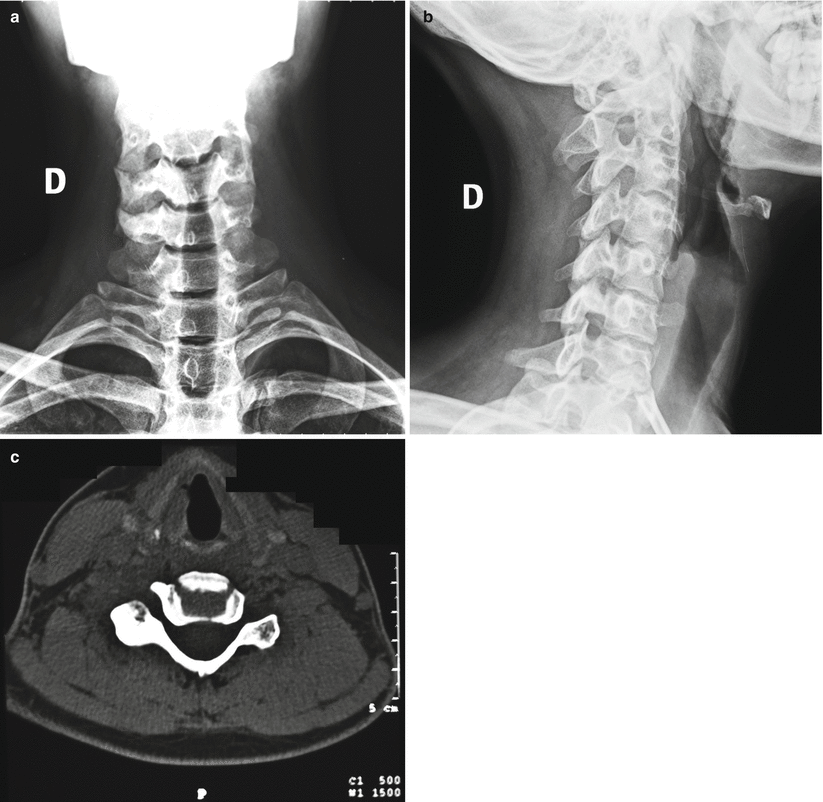

WebAbstract. Although primary bone tumors are relatively uncommon, appropriate imaging evaluation is essential when they are suspected or incidentally detected. In almost all cases, radiographs are the most appropriate initial imaging study for screening and characterization of primary bone tumors.